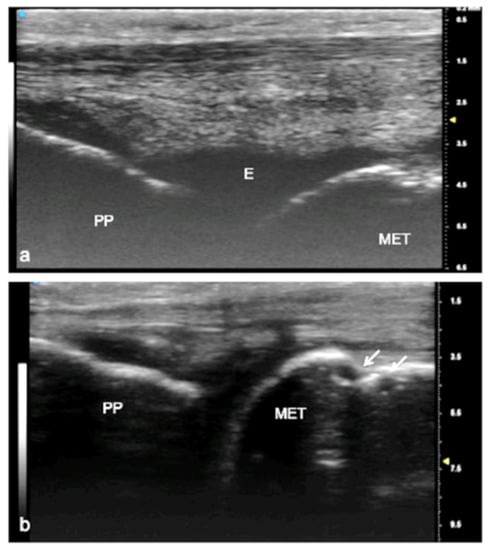

Figure 4.

Juvenile idiopathic arthritis (JIA). UHFUS gives clear details of pathological findings in pediatric patients with JIA. In (a), articular effusion (E) at the level of the metacarpal–phalangeal joint (MET-PP). In (b), osseous erosions at the level of the metacarpal head (white arrows).